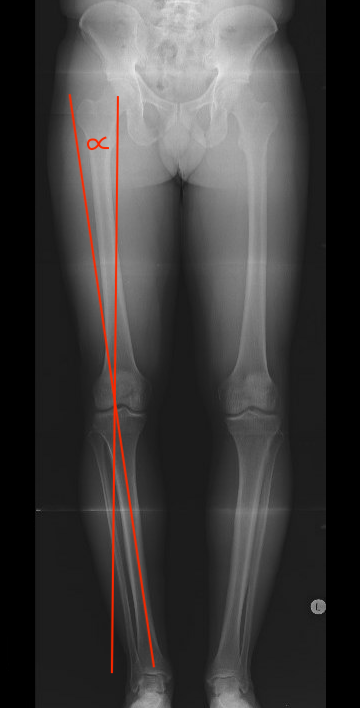

C. Fujisawa point / Weight bearing line method

Fujisawa point

- 62.5% from medial edge medial tibial plateau

- just lateral to lateral tibial spine

Line A: Center femoral head to Fujisawa point to level ankle

Line B: Center ankle joint to Fujisawa point

The angle between these lines is the angle of the desired correction